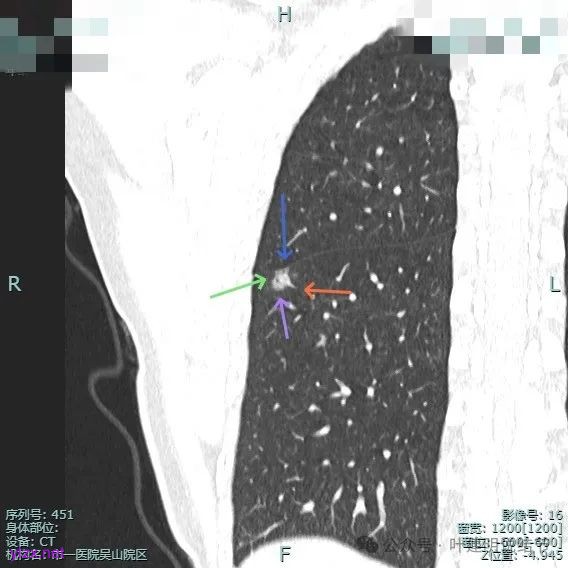

血管走向病灶,囊壁略不均。

此层见囊壁有较明显实性成分,血管进入明显。叶间裂侧平直。

混合密度,收缩力不明显,血管进入明显。

囊壁混合密度,整体轮廓清。

表面不平,血管进入,囊壁厚薄不均,紧贴叶间裂。

囊壁里面也有小空泡征。